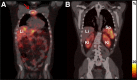

FIGURE 2.

Fused coronal SPECT/CT images of patient 1 obtained on the second day after injection of 161Tb-DOTATOC. Images showed pathologic uptake of 161Tb-DOTATOC in osseous metastasis (sternal manubrium [red arrow]) (A) and physiologic uptake of 161Tb-DOTATOC in kidneys (Ki), liver (Li), and spleen (Sp) (B).